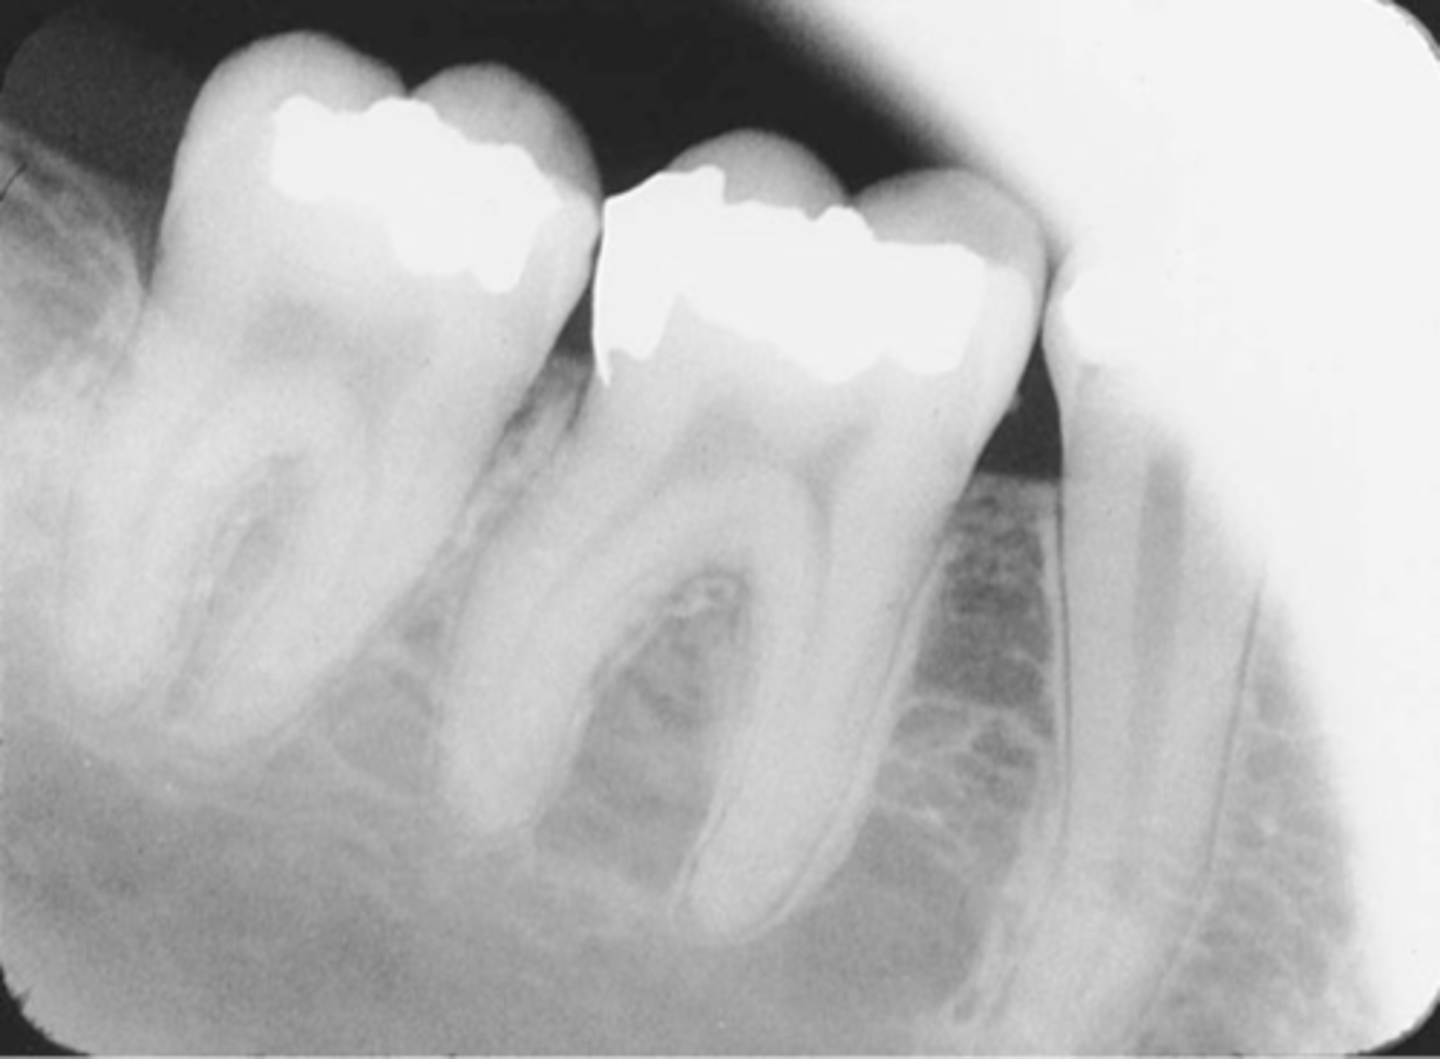

Incorrect Horizontal Angulation -->Bite-Wing

-Overlapped contacts

-CR was not directed through the interproximal spaces.